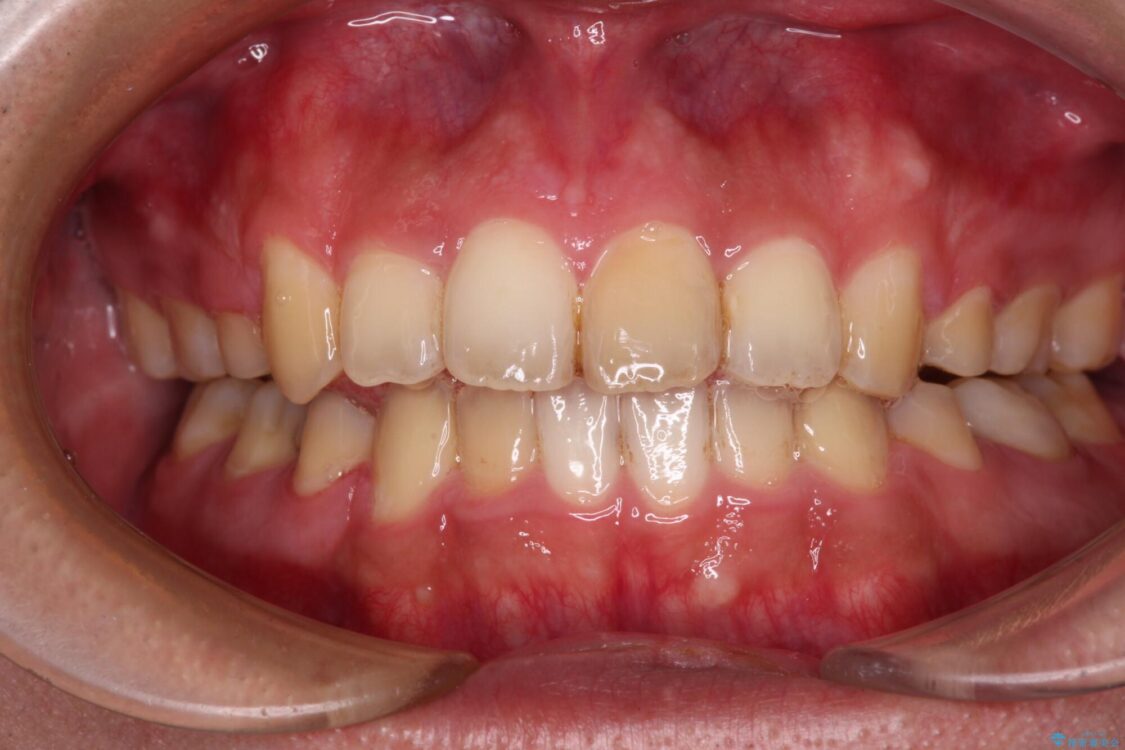

治療前

• 後戻りでデコボコの前歯 インビザライン矯正治療 治療前画像